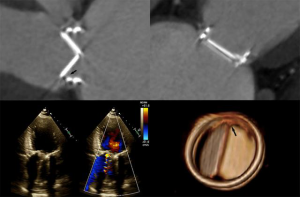

- TMVR relies on both echocardiography and CT, which are critical for patient selection, complete anatomic definition of the mitral complex, prediction of LVOT obstruction and complications diagnosis. Echocardiography is essential for procedural guidance (18,19,21,24,26,33-35). The transseptal puncture site is chosen to allow positioning of the device coaxial with the MA trajectory. A landing zone is chosen under fluoroscopic and echocardiographic guidance, monitoring for evidence of LVOT obstruction. 3D TEE is used to document full deployment of the atrial skirt and color Doppler helps detect perivalvular leaks. Sequential 2D X-plane views ascertain full leaflet capture by the device anchors, tabs or paddles, as TMVR devices do not rely on radial force for fixation. For apical delivery of TMVR devices, the location of left ventricular apical puncture is located by real time echocardiography as the operator “pokes” the ventricular apex, to identify a delivery trajectory coaxial with the MA trajectory (Figure 1) (14). TMVR procedures are divided in three categories: valve-in-valve, valve-in-ring, and valve-in-MAC (Figures 10-12, Video 4).

- The Paravalvular Leak Academic Research Consortium expert statement describes endpoint definitions and the role of imaging (36). For mitral paravalvular leaks (PVL), TEE overcomes the left atrial shadowing from the prosthesis seen in TTE and precisely identifies the PVL location and size, allowing planning of the procedure and adequate communication with the operator. CT may identify prosthetic annulus dehiscence, incomplete sealing after TMVR, or early dysfunction of the prosthesis due to pannus, sometimes mimicking a PVL (Figure 8). CT imaging uses careful reconstructions, selected image kernels and multiphase analysis to evaluate the anatomy of the leak and the surrounding structures. A PVL may be serpiginous and be located under, rather than adjacent to, the prosthetic ring, requiring dedicated oblique views for accurate imaging. Additionally, their area is dynamic and may seal during various phases of the cardiac cycle (Figure 13, Video 5). This phenomenon impacts the evaluation of the severity of mitral regurgitation, as the regurgitant jet may not be holosystolic and PISA may overestimate its severity. Additionally, the extent of associated hemolysis may be out of proportion to the size of the regurgitant jet, as estimated by color Doppler. In patients with mechanical prostheses, TEE may predict the risk of disk impingement by the closure device and is used to determine the size of the closure device. Guiding the procedure, cropped 3D TEE and 2D X-plane views are used to ascertain the passage of the wire through the PVL orifice. Once the device is deployed, an immediate assessment of mechanical leaflet mobility is performed, followed by a search for residual leaks, frequently under hemodynamic stress (volume challenge and pharmacological manipulation of the arterial pressure). While PVL closure traditionally relies on a transseptal approach, a transapical “Hopscotch” approach has been described recently, which also benefits from echocardiographic intraprocedural guidance in combination with CT angiography (37).